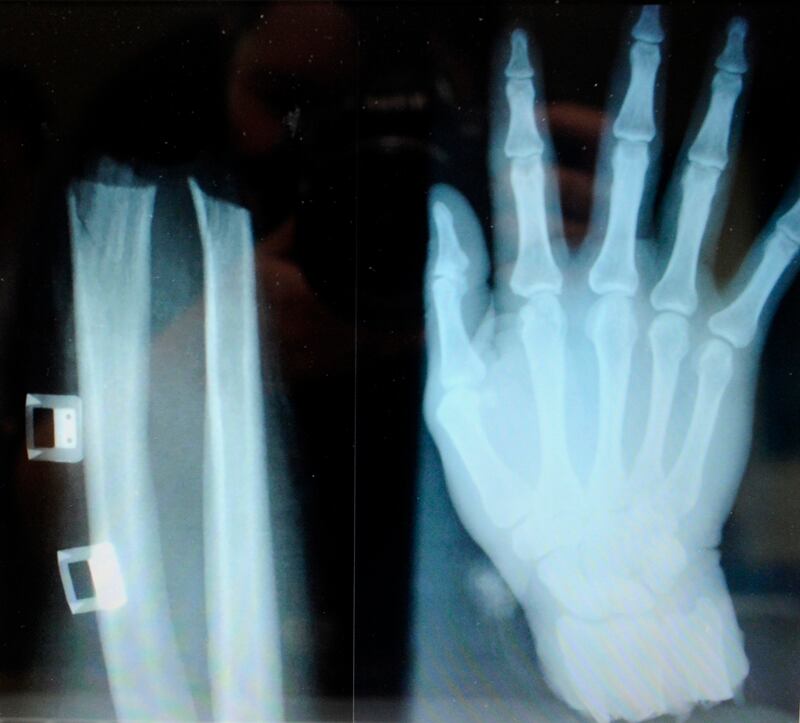

Una riña lo llevó a perder la mano izquierda y la ciencia médica lo ayudó a recuperarla, mediante una cirugía pionera en el país.

El miércoles 1.° de julio en la madrugada, un salvadoreño de 40 años, residente en Nicoya, Guanacaste, fue víctima de una agresión que le amputó la mano por completo, a la altura de la muñeca.

El corte en una muñeca fue directo y recto, a diferencia de los vistos en accidentes laborales o de tránsito, que dañan piel, nervios, tendones y hueso. Esto fue una buena noticia para los especialistas, pues al ser más directo, era más fácil controlarlo y hacer la operación.

La mano se mantuvo en bolsas dentro de una nevera, a una temperatura menor a 5 °C y el paciente fue trasladado, vía aérea, al Calderón Guardia. Un equipo de microcirugía, cirugía reconstructiva y ortopedia lo atendió, con el propósito de recuperar la mano. Y lo logró.

Una vez que el antebrazo y la mano del paciente estuvieron preparados, primero se unieron los huesos para darle firmeza y, posteriormente, tendones, nervios, venas, arterias y, finalmente, la piel.